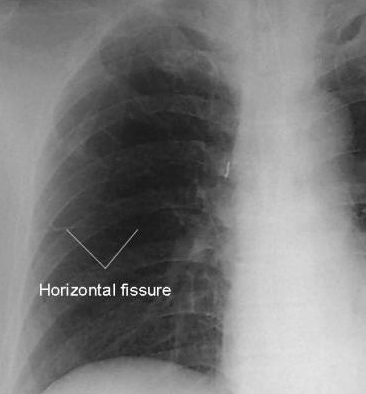

What fissure can you see on a chest x ray?

Horizontal in the right lung running towards right hilum